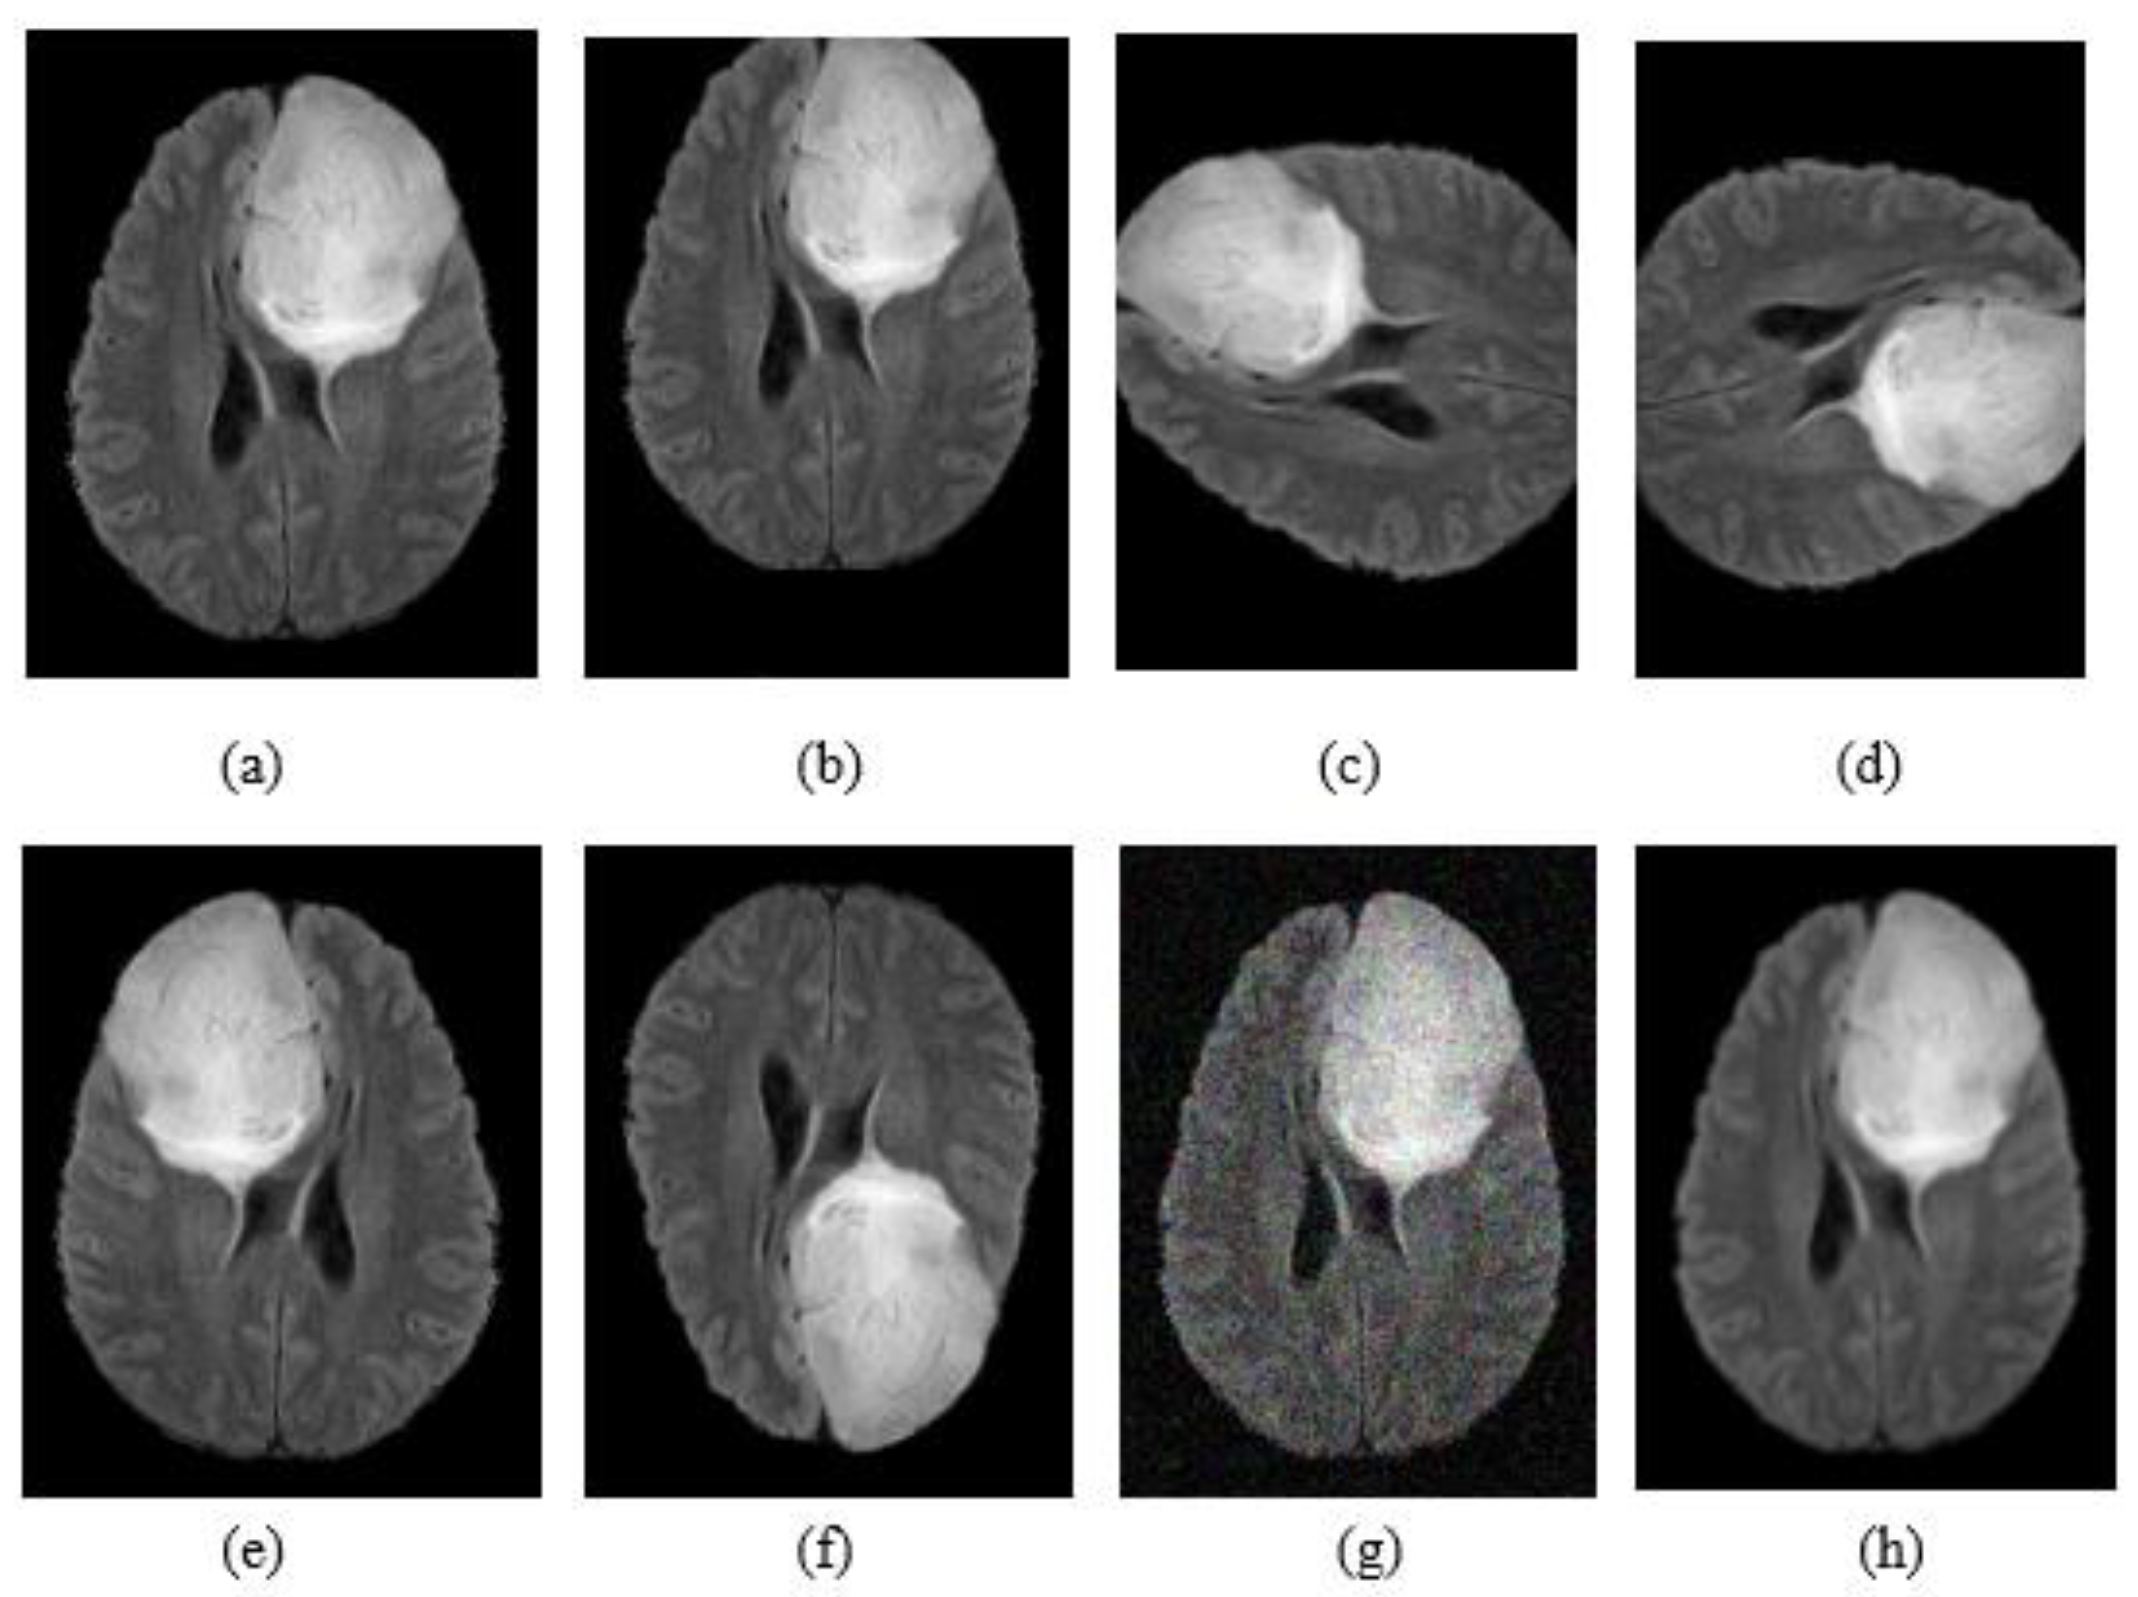

Data augmentation is a method to reduce overfitting and generate more training data from the original data. In this article, we applied the enhancement methods summarized in Table 2 and simple transformations such as flipping rotation, noise addition and shifting. Figure 2 shows an example for all the transformations applied on the original image.

Figure 2.

Example of data augmentation: (a) FLAIR image; (b) shift; (c) rotation +90°; (d) rotation -90°. (e) Flip horizontally; (f) flip vertically; (g) noise addition; (h) blur.